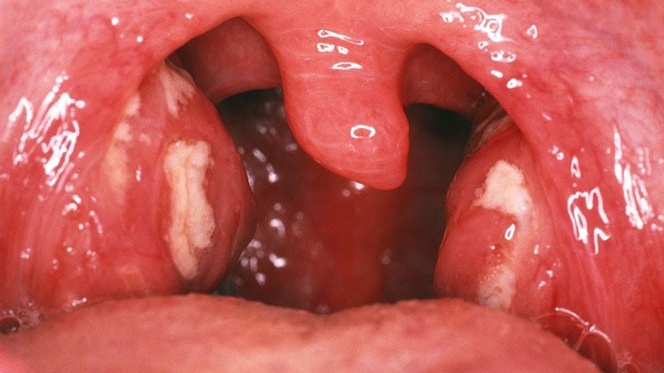

Viêm họng hạt là một căn bệnh phổ biến nhưng thường bị bỏ qua, đặc biệt là khi người bệnh chưa nhận diện được các dấu hiệu ban đầu. Trong bài viết này, chúng ta sẽ cùng tìm hiểu về hình ảnh viêm họng hạt qua các giai đoạn khác nhau, giúp bạn dễ dàng nhận diện và phân biệt bệnh.

Viêm họng hạt là một dạng viêm họng mãn tính phổ biến, gây ra những triệu chứng dai dẳng, làm giảm chất lượng cuộc sống và có thể dẫn đến nhiều biến chứng nếu không được điều trị kịp thời. Một trong những cách quan trọng giúp phát hiện bệnh sớm là thông qua việc quan sát hình ảnh viêm họng hạt, từ đó đưa ra phương pháp điều trị hợp lý. Bài viết này sẽ cung cấp những thông tin chi tiết về hình ảnh của viêm họng hạt, giúp bạn nhận diện sớm và điều trị hiệu quả.

Viêm họng hạt xảy ra khi các hạch lympho nằm trong vòm họng bị sưng viêm. Hệ thống hạch lympho này có vai trò bảo vệ cơ thể khỏi các tác nhân gây hại từ bên ngoài. Tuy nhiên, khi các tác nhân như vi khuẩn, virus hoặc các yếu tố khác tấn công, các hạch lympho sẽ phản ứng bằng cách phì đại và tạo thành các hạt đỏ, có thể nhìn thấy bằng mắt thường.

Việc quan sát hình ảnh viêm họng hạt giúp bệnh nhân nhận biết sớm tình trạng bệnh. Dưới đây là những dấu hiệu dễ nhận diện qua hình ảnh:

Trong giai đoạn cấp tính, các triệu chứng của viêm họng hạt rất dễ nhận thấy qua hình ảnh vòm họng. Một số đặc điểm nổi bật bao gồm:

Viêm họng hạt có mủ là tình trạng viêm họng hạt chuyển biến nặng, xuất hiện các nốt mủ trắng ở vòm họng. Hình ảnh điển hình bao gồm: